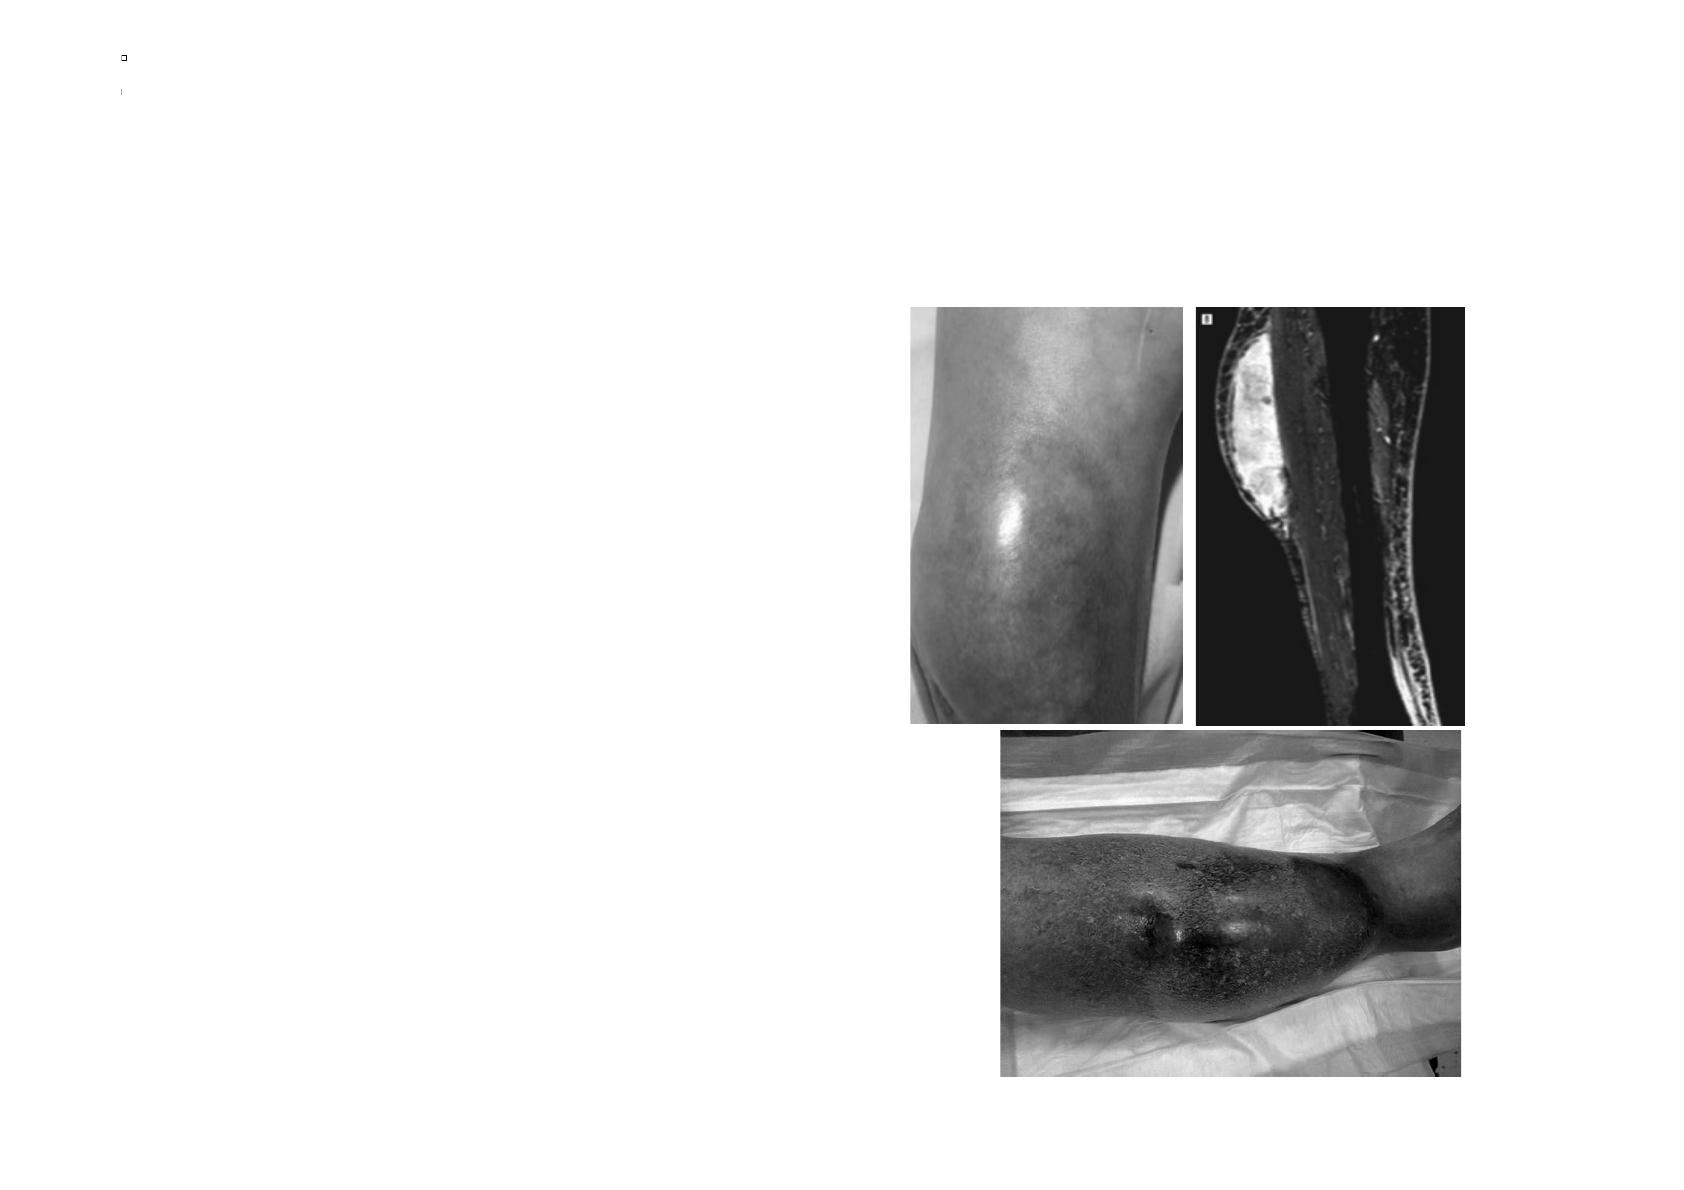

HÉMATOME DISSÉQUANT ET

SYNDROME DE MOREL-LAVALLÉE :

L’hématome disséquant

Le syndrome de Morel-Lavallée

!"#$%&#'()*++",-$.%(/(0&.+",-'.0'()'(1$()'2#$%&3&2&+'(

4%-)'(2"%2&+3'056'(

78'(#&9'.(:;<=($.+(

>'2#$%&3&2&+'($6$.0"'<(3$2?&*+(

0&250&@)'+(1&0$-A<(BCD($.50&$8-1$.%+((

E-()"F-%(/()&-1'-2<(8&.G'#'.%()'(1$(H$#F'(

+$.+(IJ62'(

K-*+("29%LJ#'('%(&')J#'(3-*+(."02&+'()-(

%&*%(

M22'-2()*$8.&+50(01$++*,-'((/("29+*3J1'(

NO($.5F*&5,-'(+&-6'.%(

PQR(/((1&0$1*+$5&.(32&?&.)'(

NO(/(0L*2('A0*+*&.()"%'2+*&.(?'2#'%-2'((&-(

NKS(((T(82'U'((

>-2"'(#&9'..'(L&+3*%$1*+$5&./((V(W(B(

+'#$*.'+(

Kaya$G,$Saurat,$JH$Arch$dermatol$2008$

Faut il inciser ou exciser le capot ?

Rapidement faire bilan échographique, scanner ou IRM pour

évaluer étendue de l’hématome